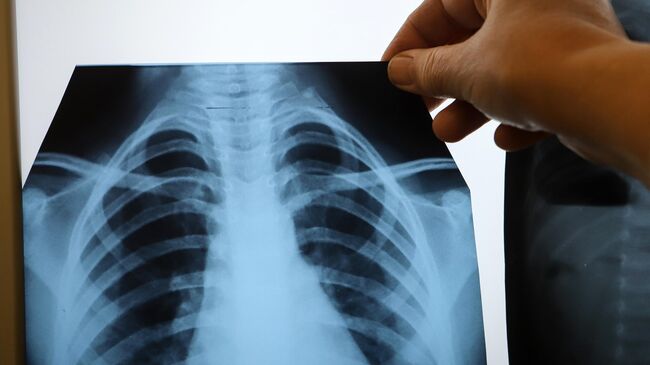

Рентгеновские технологии: усиленные экраны 35x35